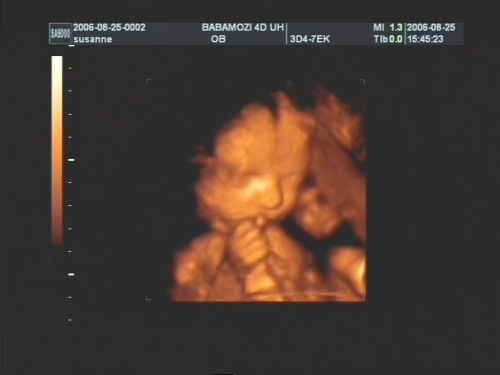

Pár kép:)

És akkor jöjjenek a képek:

Nem tudtam betelni velük,és nem tudtam választani közülük,azért van ilyen sok:

Kép Olyan kis szégyellős volt a drága,hogy állandóan takargatta a szemeit:Kép